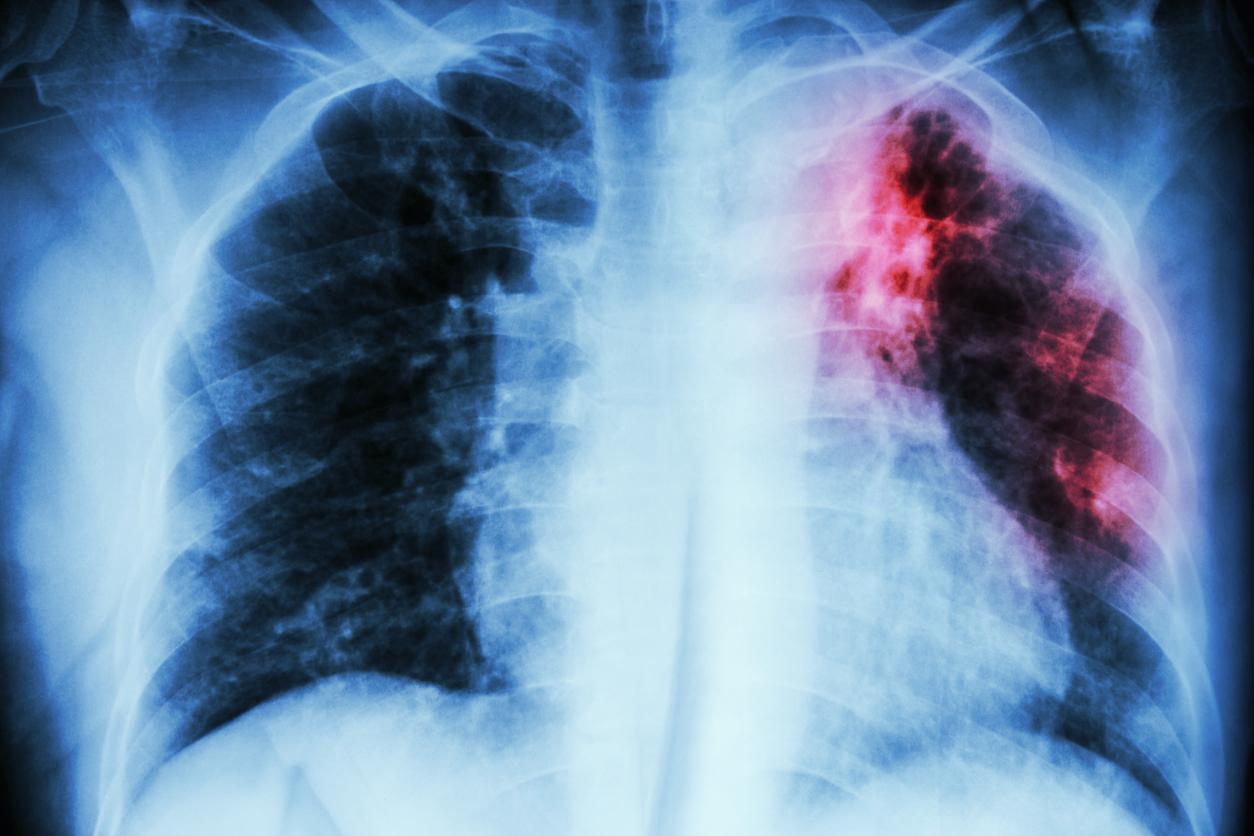

La tuberculose est due à une bactérie (Mycobacterium tuberculosis) qui touche le plus souvent les poumons. C’est une maladie que l’on peut prévenir et soigner, indique l’OMS. Elle se transmet d’une personne à l’autre par voie aérienne : "Quand une personne ayant une tuberculose pulmonaire tousse, éternue ou crache, elle projette des bacilles tuberculeux dans l’air. Il suffit d’en inhaler seulement quelques-uns pour s’infecter".

Les radiographies du thorax de 498 patients ont été analysées rétrospectivement. Cinquante-sept (11 %) de ces patients avaient reçu un diagnostic de tuberculose, dont 41 cliniquement et 16 par des tests PCR (Xpert MTB/Rif). Ce test détecte simultanément le complexe Mycobacterium tuberculosis (MTBC) et la résistance à la rifampicine (RIF), spécifiques de la tuberculose, en moins de 2 heures.

D’après l'expérience, le logiciel d'IA a correctement identifié 75 % de tous les cas confirmés par PCR et 85,7 % des cas non tuberculeux. Le radiologue moins expérimenté a lui correctement identifié 62,5 % des cas confirmés par PCR et correctement identifié 91,7 % des cas non tuberculeux. Les évaluations du radiologue expérimenté étaient eux de 75 % pour les cas confirmés par PCR et de 82 % pour les cas non tuberculeux.